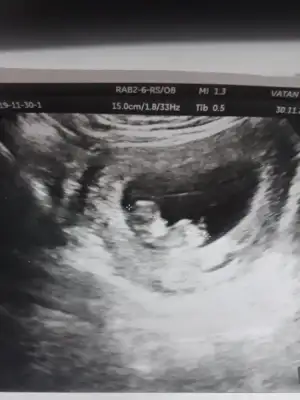

Biri 9+5 biri de 11+5. Yan donmus gibi belli oluyor mu bilemedimTekrar atsana foto

Kız gibiBiri 9+5 biri de 11+5. Yan donmus gibi belli oluyor mu bilemedim![]()